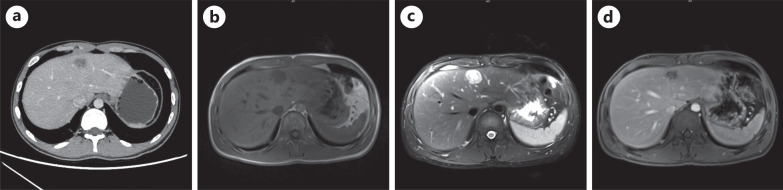

Case report: We herein report a case involving a 23-year-old Tibetan man who was admitted to the hospital with swelling, pain, and limited movement of the right knee joint. Imaging revealed a tumor in the right knee, and preoperative examinations detected multiple liver lesions. Contrast-enhanced ultrasound showed high enhancement with a thick rim and uneven iso-enhancement in the center during the arterial phase, slow washout of the rim in the portal to delayed phases, and uneven low enhancement centrally. Based on these imaging findings and the patient's history, hepatic tuberculosis was considered, although a tumor could not be ruled out. Laboratory tests - including routine blood, liver function - were normal, and most tumor markers were normal except neuron-specific enolase. The patient underwent surgical resection of the knee tumor, and pathological diagnosis confirmed CCS. The liver lesions were further evaluated with contrast-enhanced computed tomography and enhanced magnetic resonance imaging, but a definitive diagnosis remained elusive. Ultimately, ultrasound-guided needle biopsy confirmed liver metastasis from CCS.